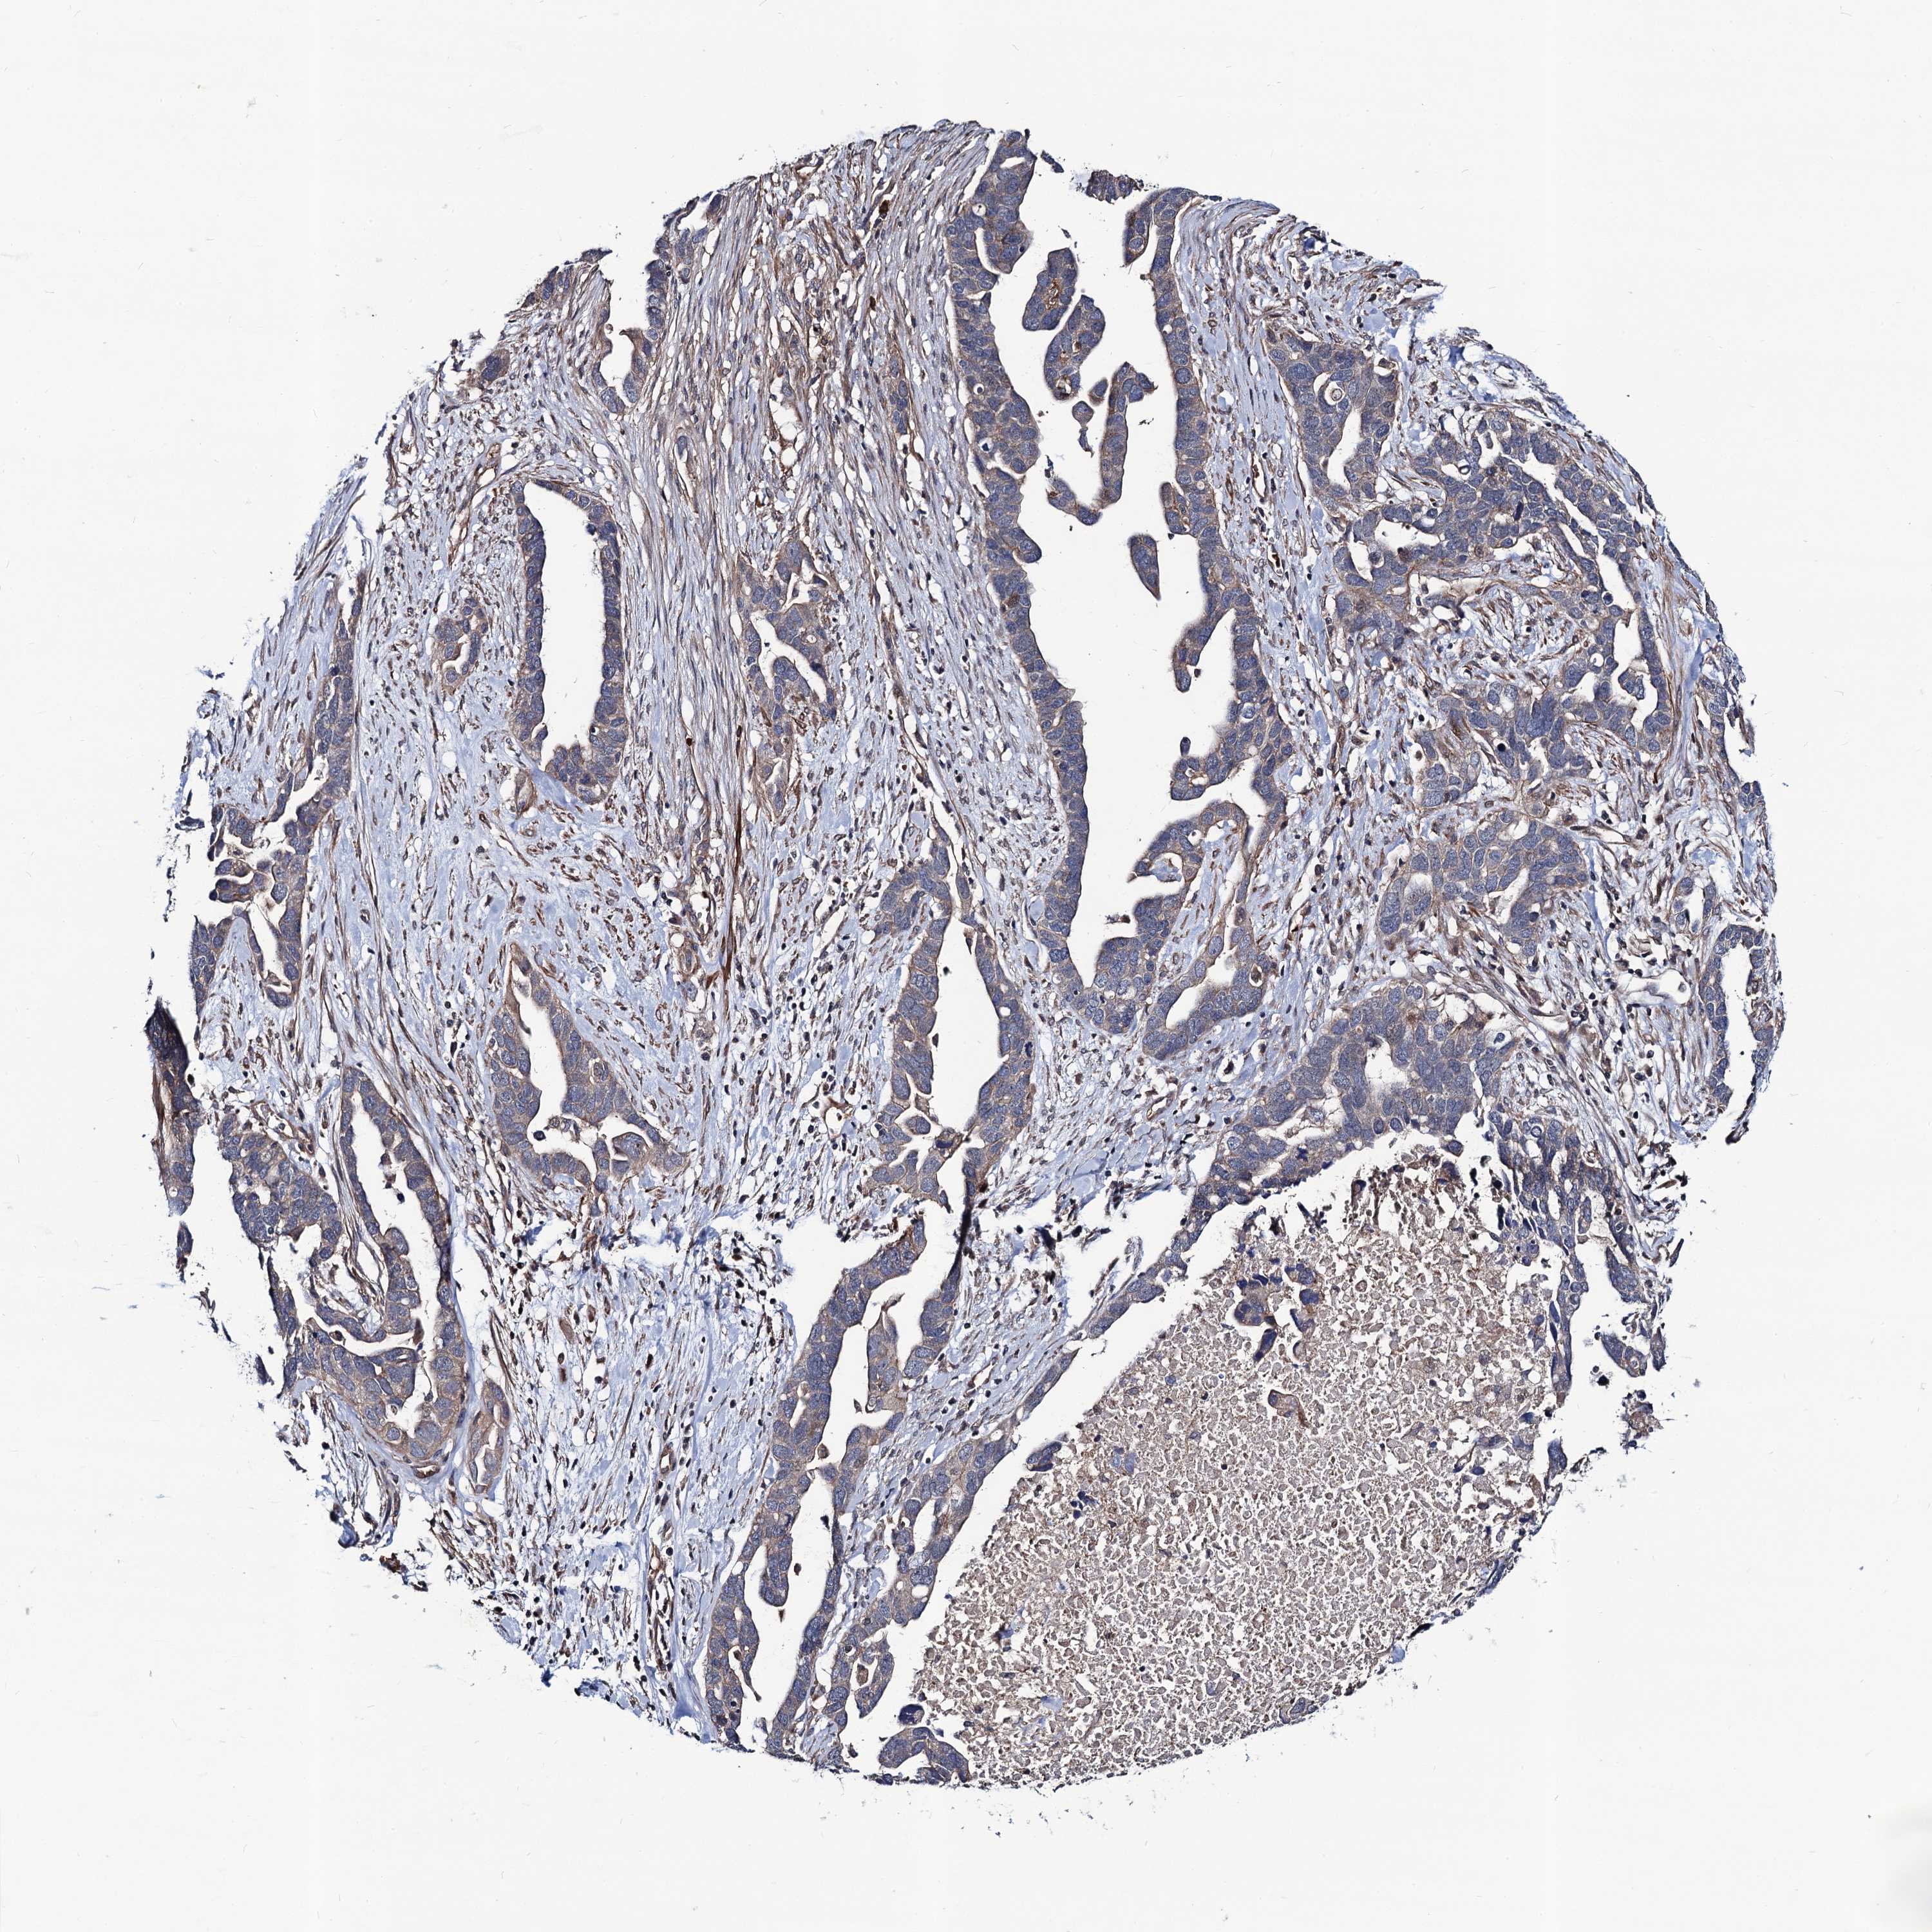

OVARIAN CANCER - Protein expressioni

A mouse-over function shows sample information and annotation data. Click on an image to view it in a full screen mode. Samples can be filtered based on level of antibody staining by selecting one or several of the following categories: high, medium, low and not detected. The assay and annotation is described here.

Note that samples used for immunohistochemistry by the Human Protein Atlas do not correspond to samples in the TCGA dataset.

Antibody stainingi

Antibody staining in the annotated cell types in the current human tissue is reported as not detected, low, medium, or high, based on conventional immunohistochemistry profiling in selected tissues. This score is based on the combination of the staining intensity and fraction of stained cells.

Each image is clickable and will lead to virtual microscopy that enables deeper exploration of all samples and also displays staining intensity scores, fraction scores and subcellular localization as well as patient and tissue information for each sample.

Antibody HPA041507

Antibody HPA041599

Cystadenocarcinoma, serous, NOS

Carcinoma, endometroid

Cystadenocarcinoma, mucinous, NOS

Carcinoma, NOS